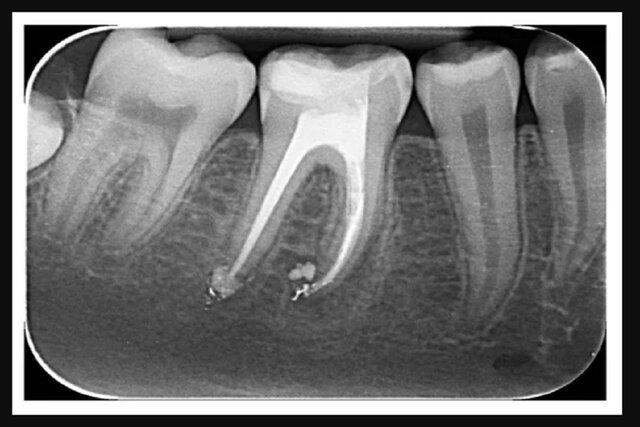

پژوهشگران "مؤسسه علوم هند" در بررسی جدیدی، از نانورباتها برای درمان کانال ریشه دندان استفاده کردهاند.

چنین عفونتهایی میتوانند از باکتریهای باقیمانده در اعماق لولههای ریز در عاج دندان ایجاد شوند که به دلیل پیچیده بودن و هندسه باریک این لولهها، ضدعفونی کردن آنها حتی با روشهای مرسوم، سخت است اما به لطف تلاشهای گروهی از پژوهشگران "مؤسسه علوم هند"(IISc)، این شکستهای پس از درمان را میتوان با رباتهایی در اندازه نانو که با نیروی مغناطیسی کنترل میشوند، کاهش داد.

"امباریش گوش"(Ambarish Ghosh) و گروهش، نانورباتهایی را توسعه دادند که به اندازه کافی کوچک هستند تا در لولههای عاج دندان قرار بگیرند و به باکتریها برسند تا آنها را از بین ببرند. این نانورباتها را میتوان طی درمان ریشه به کار برد و آنها را به صورت خارجی کنترل کرد. همچنین، نانورباتها میتوانند هنگام ضدعفونی کردن دندان آسیبدیده، امکان کنترل دقیق را برای دندانپزشک فراهم کنند.